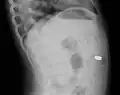

A coin seen on lateral CXR in the esophagus

Lateral X ray showing a 9mm battery in the intestines